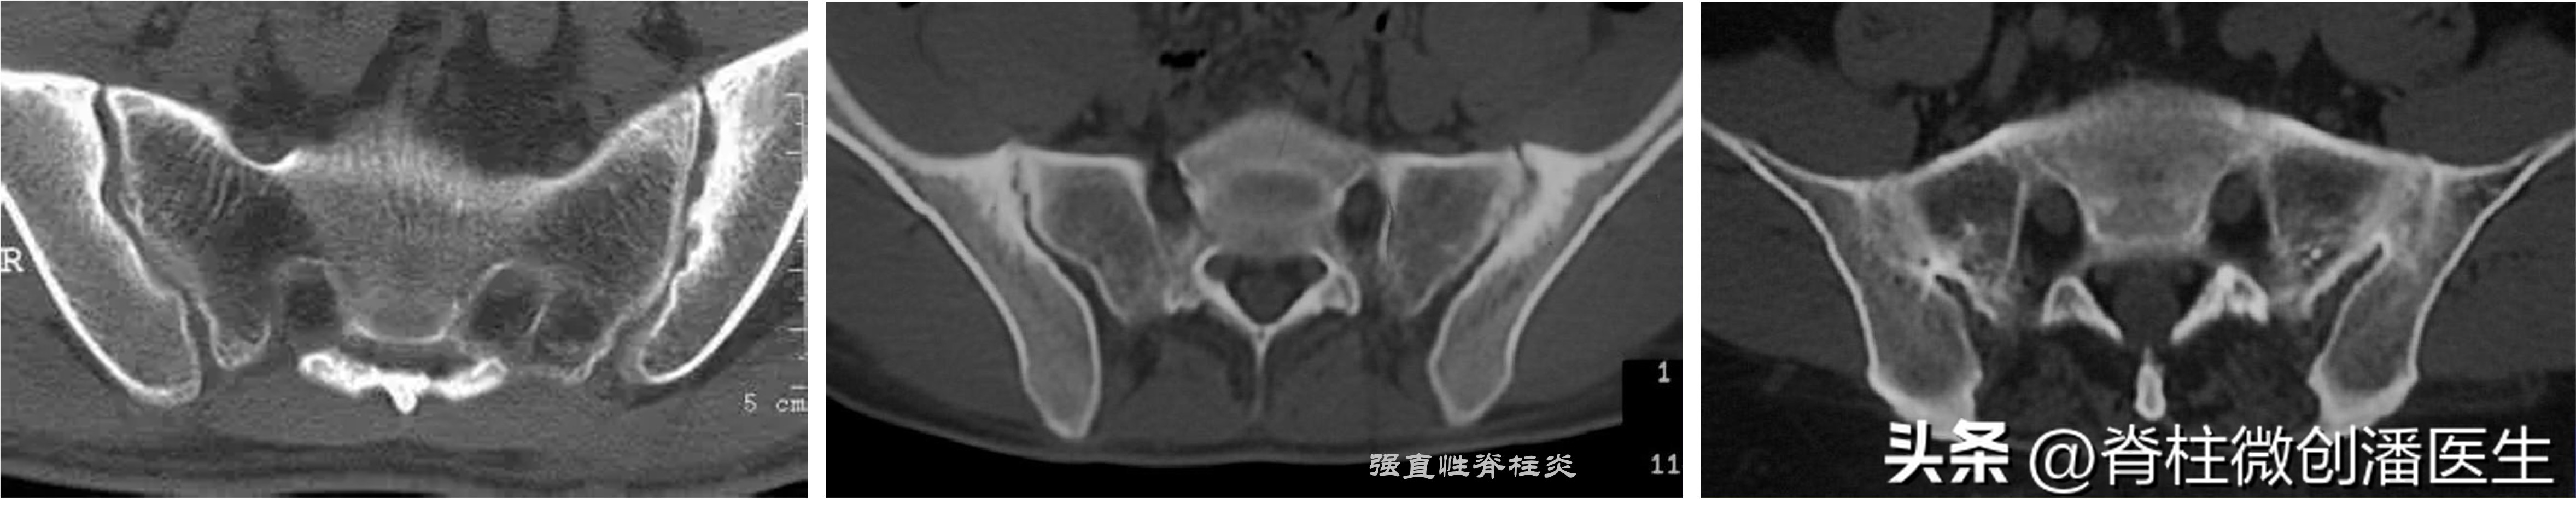

当病人主诉骶髂关节部位疼痛,经检查疼痛的根源主要是在骶髂关节时,应投照骨盆正位片,必要时可投照骶髂关节的专用体位片,即患者坐在X片盒上,身体略前倾,X线球管自后上方对准健侧的骼后上棘,使其与患侧骶髂关节呈45°角摄片,可较清晰地显示骶髂关节面。或 直接选择更为直观的骶髂关节CT检查。

骶髂关节的X片或CT除可协助确定上述骶髂关节病变外,还可同时确定一些侵犯骶髂关节的其他疾病:①骶髂关节松弛:多见于经产妇,骶髂关节间隙增宽,可伴有退行性变,同时耻骨联合处也可退变。松弛明显者,单足站立位时投照,可见持重侧耻骨上移。②骶髂关节结核:常为单侧,且多侵犯关节的下部,关节边缘出现虫蚀样病灶,以后关节破坏,间隙增宽并可有死骨形成,可伴有寒性脓肿。③ 强直性脊柱炎:双侧骶髂关节受侵,初期关节间隙模糊,逐渐出现串珠样改变,最后关节硬化、间隙消失。④Reiter综合征:骶髂关节面破坏,周围骨质硬化明显,临床上伴有尿道炎、结膜炎等症状。